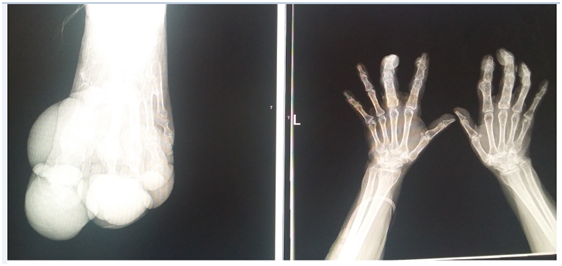

Female of 59 years old, exposed to biomass smoke (index=100 hrs/year), followed as Chronic Obstructive Lung Disease during 9 years; her main symptom has been dyspnea, vital signs HR 86 per min, RR 20 per min, 110/78 mmHg, body temperature 36.6°C, very severe obstruction in spirometry, low Diffusion Capacity, increased Residual Volume, Pulmonary Arterial hypertension by echocardiography (47 mmHg) and arterial gases pH 7.38, PaCO2= 47 mmHg, PaO2 66 mmHg, HCO3 =21.6 and O2 saturation 92.5% with oxygen supply. Radiographic studies Figure 1 showed, bullous emphysema at left lung in conventional chest radiography; and, neurofibromatosis lesions in both hands (Figure 2) and feet (Figure 3) and Computed tomography revealing bilateral emphysema and bullae (Figure 4).

Figure 2 Neurofibromatosis Lesions.

Figure 3 Bullous emphysema 1.

Figure 4 Bullous emphysema 2.